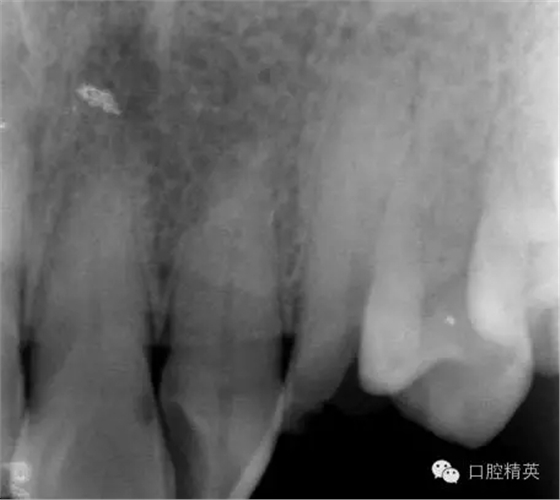

圖2 治療前X片: 23殘根,根尖區(qū)骨密度降低.

口內(nèi)檢查: 23殘根,位于齦上3MM,根管口探無(wú)反應(yīng),叩(+-),無(wú)松動(dòng),牙周無(wú)紅腫.X片示:23根管無(wú)阻射,根尖骨密度降低.